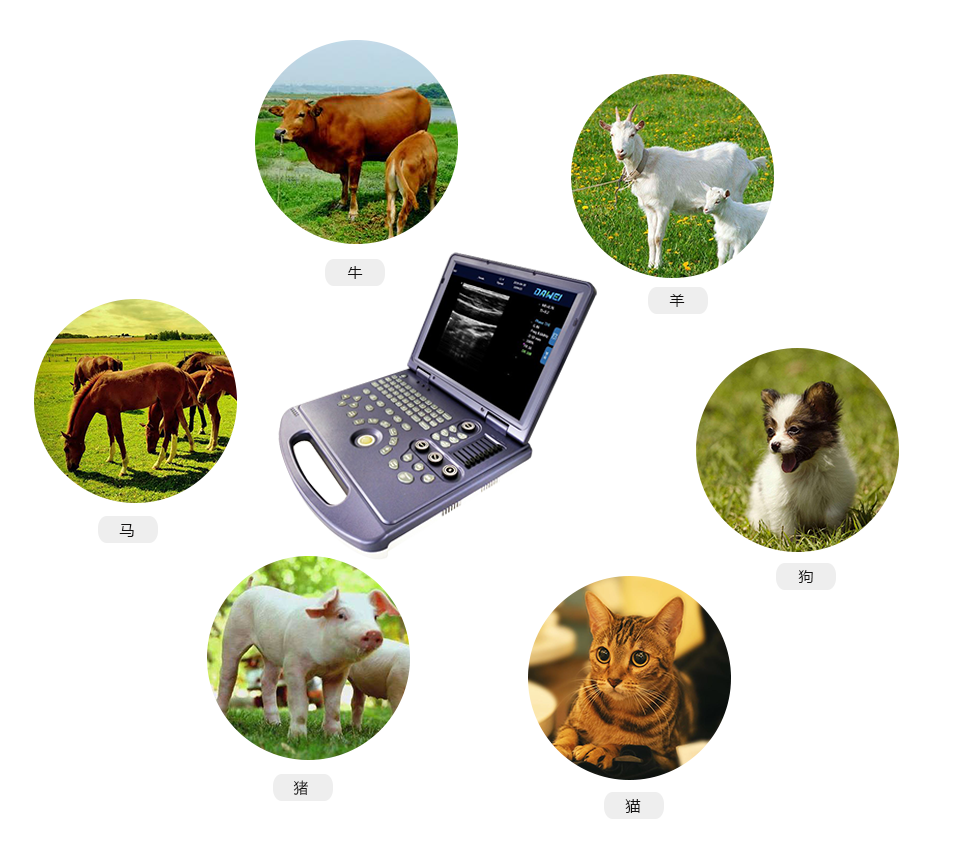

MU15便攜筆記本式獸用B超機

動物寵物超聲診斷儀

·具有專業的動物產科軟件包,分別是狗、貓、馬、牛、羊

適用對象:

牛羊馬豬犬貓及多種家禽、實驗動物、野生動物、及部分水生動物。